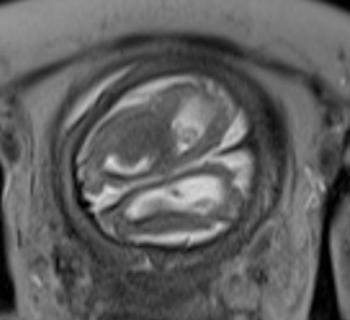

In a third study, ultrasound and fetal MRI were performed on pregnant patients with Zika virus infection at different gestational ages. Once the babies were born, they underwent ultrasound, CT and MRI. The researchers then created 3-D virtual and physical models of the skulls. More than half the babies had microcephaly, brain calcifications and loss of brain tissue volume, along with other structural changes.

"The emergence of Zika virus in the Americas has coincided with increased reports of babies born with microcephaly," said study author Heron Werner Jr., M.D., Ph.D., from the Department of Radiology at Clínica de Diagnóstico por Imagem. "An early diagnosis may help in treating these babies after birth. Moreover, the knowledge of abnormalities present in the central nervous system may give hints about the pathophysiology of the disease."